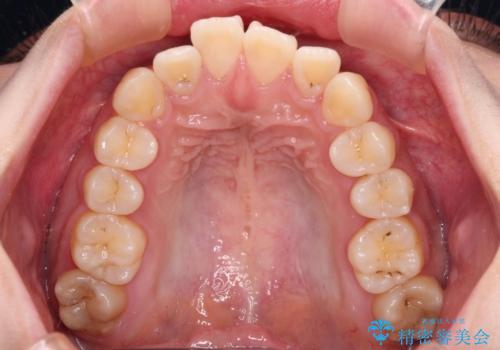

- 前歯の捻れを気にして来院された患者様です。

上顎前歯が捻れて前方に飛び出しており、下顎前歯もそれに沿うようにデコボコとなっていました。

IPR(歯と歯の間を削る処置)によりスペースを獲得して下顎前歯のデコボコを改善し、上顎前歯は下顎前歯と接する位置にまで引っ込めるように設定し、インビザラインにて矯正治療を行うこととしました。